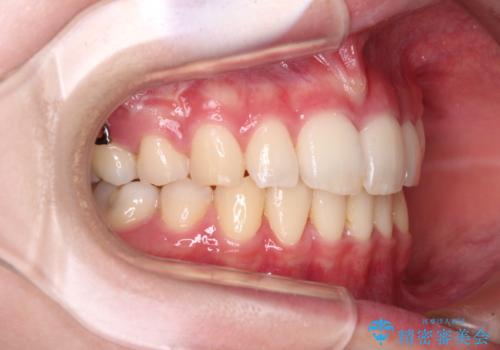

治療途中で転院 抜歯矯正の仕上げ治療

- 地元で抜歯治療を行っている途中、東京へ転職したため治療を継続して欲しいとのことで来院された患者様です。

出っ歯を抜歯矯正にて治療をしていらっしゃいましたが、抜歯スペースが少し残っていたため、閉じて歯列を仕上げていくこととしました。